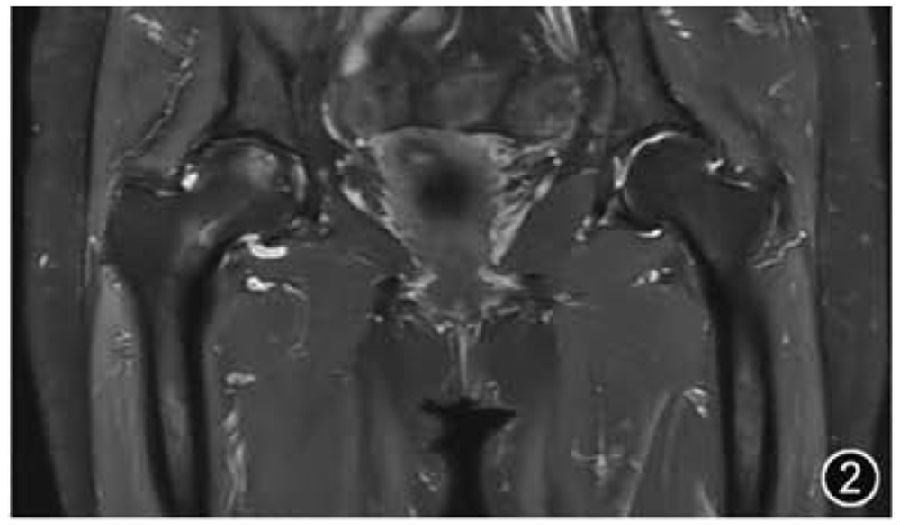

5.股骨头缺血性坏死:由于股骨头缺血性坏死往往是双侧发病,因此在影像检查时应选择双髋关节MRI检查,且应特别注意评估双侧髋关节的对称性。典型的股骨头缺血性坏死在MRI上表现为新月形软骨下病变,周围有低信号边缘,在T2WI上具有特征性的“双线征”(图6)。应描述骨坏死的位置和大小、受影响的股骨头体积的估计百分比(<15%、15%~30%、>30%)及病变所处阶段。由于股骨头塌陷代表更晚期疾病和不可逆转的损伤,因此股骨头是否出现塌陷应当描述(<2 mm为轻度,≥2 mm为中重度),若存在继发性髋关节OA和股骨头碎裂也应描述。骨坏死的主要信号可用于评估所处阶段,脂肪信号提示超急性或愈合期病变,骨髓水肿信号提示急性或亚急性期病变,而骨质硬化信号提示病变处于慢性期。

图6 股骨头缺血性坏死MRI图像。横断面T2WI示双侧股骨头见两条条带状内高外低并行高信号,为双线征